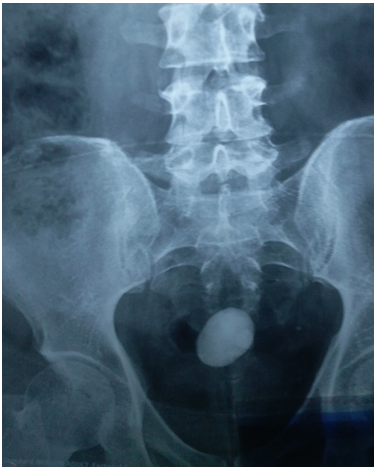

45 years old male patient came to urology outpatient complaining of recurrent right flank pain for several months, no fever or hematuria, no significant medical or surgical history. Physical examination was unremarkable, serum creatinin 1.1mg/dl , urine analysis showed microscopic hematuria, urine culture was negative, ultrasound reveals multiple right renal stones with dilated extrarenal pelvis, plain x ray & intravenous pyelography performed Figure1 (A & B). All treatment options explained to the patient and after discussion he elected to undergo laparoscopic peylolithotomy. Transperitoneal laparoscopic pyelolithotomy was performed in lateral position with Rt. Flank tilted 45 degrees using 4 ports. multiple renal pelvis and calyceal stones extracted and putted in a bag made of No 6 surgical glove (Figure 2) after closure of the pyelotomy by intracorporeal sutures the bag containing the stones extracted through the umbilical port after enlarging it (Figure 2), during extraction the bag was broken and some stones escaped to the abdomen. Another bag replaced and most of the stones extracted searching for the remaining stones in the abdomen was frustrating and we decided to terminate the procedure and closing the port sites. The post-operative course is unremarkable and patient discharged in fifth post-operative day. Follow up plain x-ray after one month revealed tow round stones with 30 and 10mm maximum diameter lying deep in the pelvis (Figure 3), after discussion with the patient about the possible complications of those stones he agree to underwent open extraction by low midline incision and stones extracted.

Figure 3 Post operative x ray showing lost stones in the pelvis.